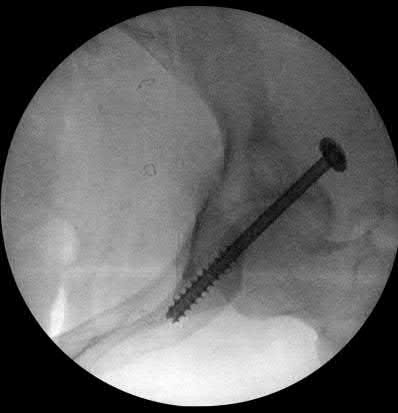

A 12-year-old obese boy presents with vague left thigh and knee pain. He is diagnosed with a Slipped Capital Femoral Epiphysis (SCFE) as seen in similar clinical scenarios.

During percutaneous in-situ fixation, unrecognized penetration of the guide wire into the hip joint occurs. What is the most likely specific complication resulting from this technical error?

Chondrolysis is a severe complication of SCFE characterized by rapid destruction of the articular cartilage. While it can occur idiopathically, its most established iatrogenic cause is unrecognized intra-articular hardware penetration. The 'approach-withdraw' fluoroscopic technique is required during pinning to assure pins are entirely intraosseous. Avascular necrosis (AVN) is usually due to damage to the epiphyseal blood supply (retinacular vessels) secondary to the initial displacement, forceful closed reduction, or posterosuperior pin placement.